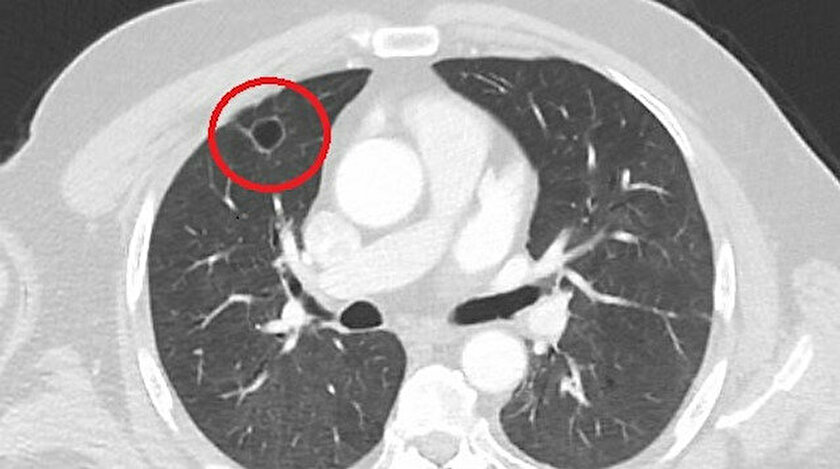

Kent dışında çalışan N.T.'nin, göğüs ağrısı şikayetiyle gittiği hastanede çekilen tomografisinde sağ akciğerinde 4 santimetre çapında tümör tespit edildi. Kanser olabileceği şüphesiyle yapılan ileri tetkikler sonrası N. T.'ye akciğer kanseri teşhisi kondu ve acil ameliyat kararı verildi.

Ameliyat öncesi N.T.'nin Covid-19 testi pozitif çıkınca operasyon ertelendi. Koronavirüs tedavisine başlanan N.T.'nin son testi negatif çıktı. Dr. Fatoş Kozanlı, tedavi sonrası tomografisi çekilen N.T.'nin akciğerindeki tümörün yok olduğunu gördü. Kozanlı, N.T.'nin kendilerine başvurduğunda koronavirüs belirtisi olmadığını ancak ameliyat öncesi PCR testi yaptıklarını söyledi. Koronavirüs tedavisinin ardından ortaya çıkan sonucun kendisini de şaşırttığını belirten Kozanlı, şunları söyledi:

"Hastamız, çalıştığı başka bir kentte göğsünden darbe alıyor ve ağrıları geçmeyince bir üniversite hastanesine başvuruyor. Burada hastaya bir akciğer grafisi çekiliyor. Sağ akciğerinde bir kitleye rastlanıyor. Daha sonra hastaya, bir akciğer tomografisi çekiliyor ve göğüs cerrahisi için önemli büyüklükte olan 4 santimetre çapında, akciğer kanserine benzer özellikte radyolojik bulgular olan bir kitle tespit ediliyor. Daha sonra hastaya yapılan ileri tetkiklerde akciğer kanseri teşhisi konuluyor. Hastaya bir cerrahi planlanıyor. Hasta Kahramanmaraşlı olduğu için kendi memleketine gelmeyi tercih ediyor. Bize başvurdu ve göğüs ağrısı şikayeti vardı. Öksürük, nefes darlığı, balgam çıkarma, ateş gibi şikayetleri yoktu. Hastayı biz de değerlendirdik ve ameliyat olmasına karar verdik. Çünkü akciğer kanserine çok benzer radyolojik bulguları vardı. Sağlık Bakanlığımızın kuralları gereği her hastayı ameliyat öncesi PCR testi yapılır.

Biz de ameliyat gecesi hastadan PCR testi aldık ve testi pozitif geldi. Ameliyatımızı 14 gün erteledik ve hastamıza koronavirüs tedavisi uygulandı. Hasta 14'üncü gün tekrar bize başvurdu ve yapılan PCR testi negatif çıktı. Yeni bir tomografi çektik ve tümörün tamamen ortadan kalktığını gördük. Şimdi sonuç bilgilerinden başlangıca gittiğimizde, bu bir akciğer kanseri olsaydı, ortadan kalkması mümkün değildi. Başka bir patolojiye bağlı durum olsaydı, yine verdiğimiz tedaviyle ortadan kalkmasını çok beklemeyiz. Antiviral tedavisi verdik ve hastanın radyolojik bulguları neredeyse tamamen normale döndü. Hastaya bunu izah ettik, 'Dünya literatüründe hiç görülmeyen bir radyolojik bulgu' diyerek. Bu gördüğümüz manzara artık hastanın akciğer grafisinde yok, akciğer kanseri değil. "